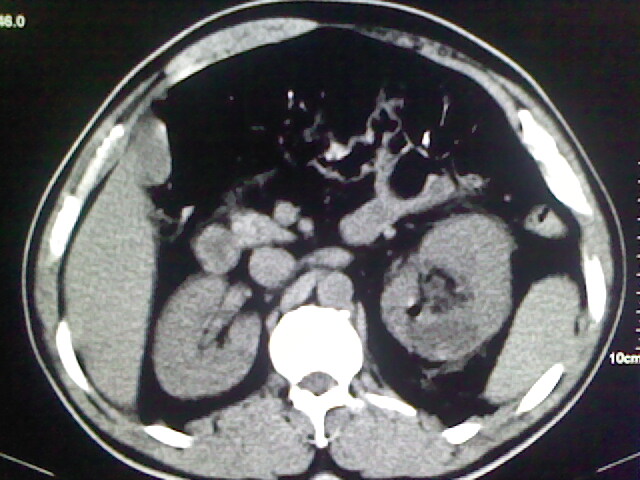

以下是引用zsl6918在2009-2-7 7:29:00的发言:[br]请提供介入的方式方法,肾及输尿管改变考虑与介入损伤有关,漏了,尿液外渗。

以下是引用余辉在2009-2-7 8:27:00的发言:[br]可能是硬化剂烧穿囊壁进入肾盂输尿管了,尿漏。不除外介入或碎石术后合并感染[br]患者术后怀疑结石,接着就碎石了?就怀疑没有确诊吗?碎石用的什么方法?气压弹道还是体外超声?如果这样的话责任人都难找

以下是引用随光逐影在2009-2-7 8:46:00的发言:[br]支持3楼意见。[br]另:不排除左肾及肾周感染可能。